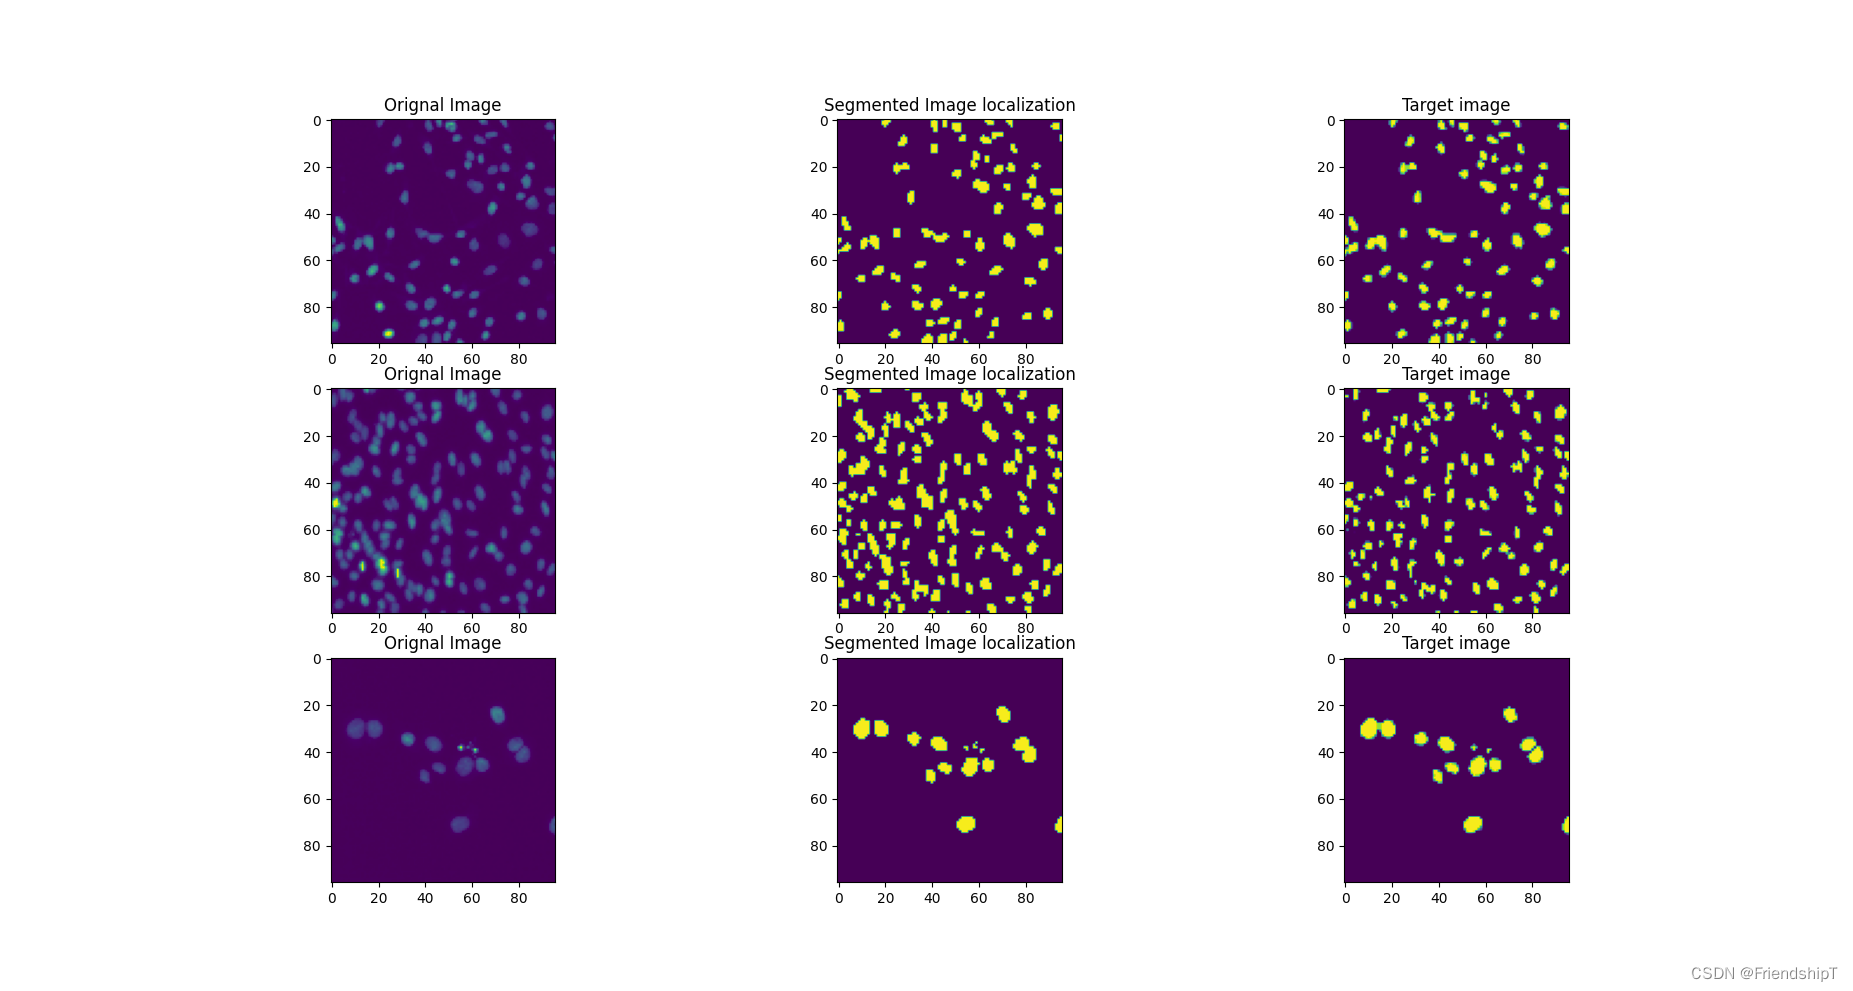

def plot_examples(datax, datay, model,num_examples=6):

fig, ax = plt.subplots(nrows=num_examples, ncols=3, figsize=(18,4*num_examples))

m = datax.shape[0]

for row_num in range(num_examples):

image_indx = np.random.randint(m)

image_arr = model(datax[image_indx:image_indx+1]).squeeze(0).detach().cpu().numpy()

ax[row_num][0].imshow(np.transpose(datax[image_indx].cpu().numpy(), (1,2,0))[:,:,0])

ax[row_num][0].set_title("Orignal Image")

ax[row_num][1].imshow(np.squeeze((image_arr > 0.40)[0,:,:].astype(int)))

ax[row_num][1].set_title("Segmented Image localization")

ax[row_num][2].imshow(np.transpose(datay[image_indx].cpu().numpy(), (1,2,0))[:,:,0])

ax[row_num][2].set_title("Target image")

plt.show()